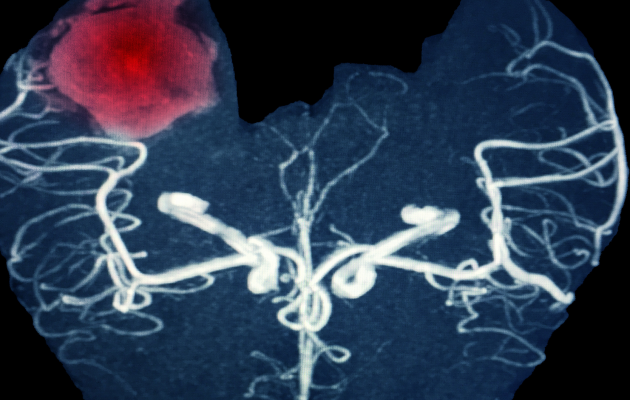

Definition and Use: Cranial CT is the most commonly used method for diagnosing brain hemorrhage. It provides cross-sectional images of brain tissue and quickly identifies bleeding location and spread.

Definition and Use: Cranial MRI is used for a more detailed evaluation. Magnetic resonance imaging provides high-resolution images of brain tissue and vessels.

Advantages: MRI scans can reveal underlying causes such as aneurysms or tumors and provide detailed visualization of brain changes.